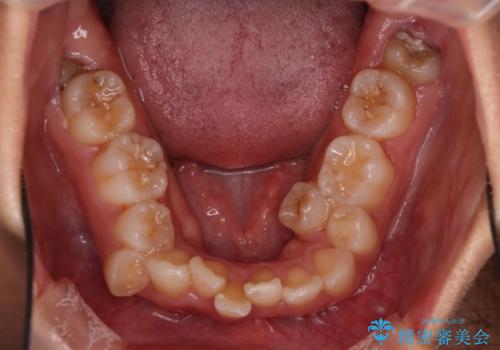

- 前歯の凸凹を主訴に来院されました。

抜歯を行い、ワイヤー矯正にて治療を行いました。

凸凹もなくなり、歯磨きもしやすくなったと喜んでいただきました。